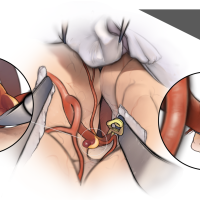

FEN2022シリーズ